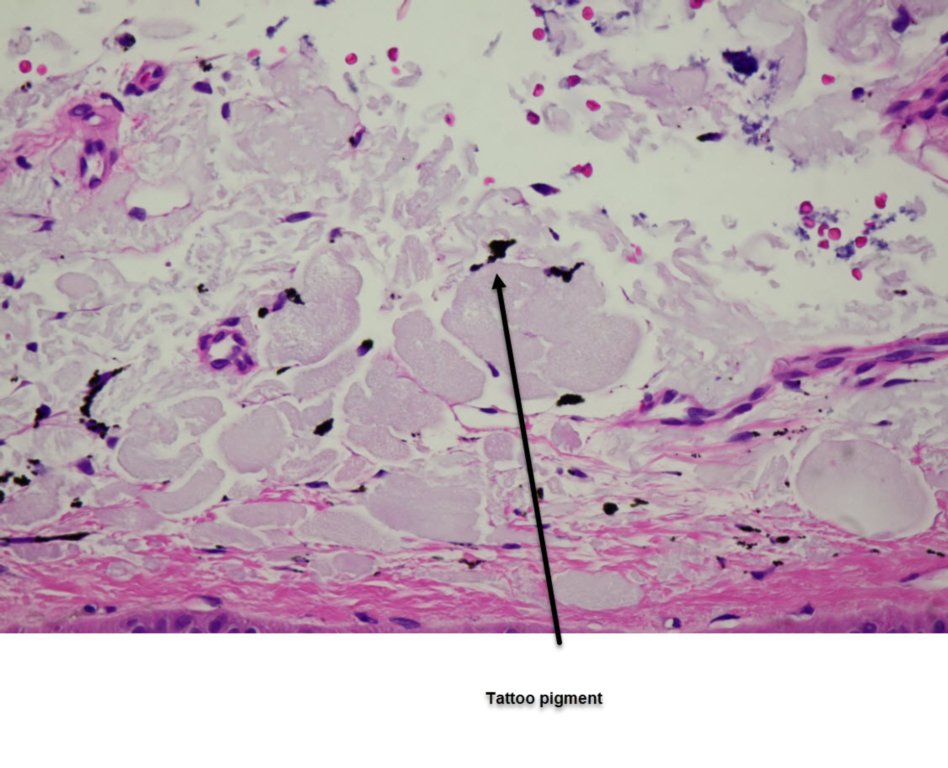

Man aged 84, previous melanomas including blue nevus like  metastatic melanomas on the leg which I presented last year. This time he comes in pointing out 3 blue lesions on his forearm. He denied seeing them before and they had not previously been noted when a skin check was performed. It was thought they were metastatic but histology of all three showed dermal pigmentation of a tattoo.

Foreign bodies can present like this but metastases rather than multiple blue nevi is the likeliest pigmented lesion to present like this.